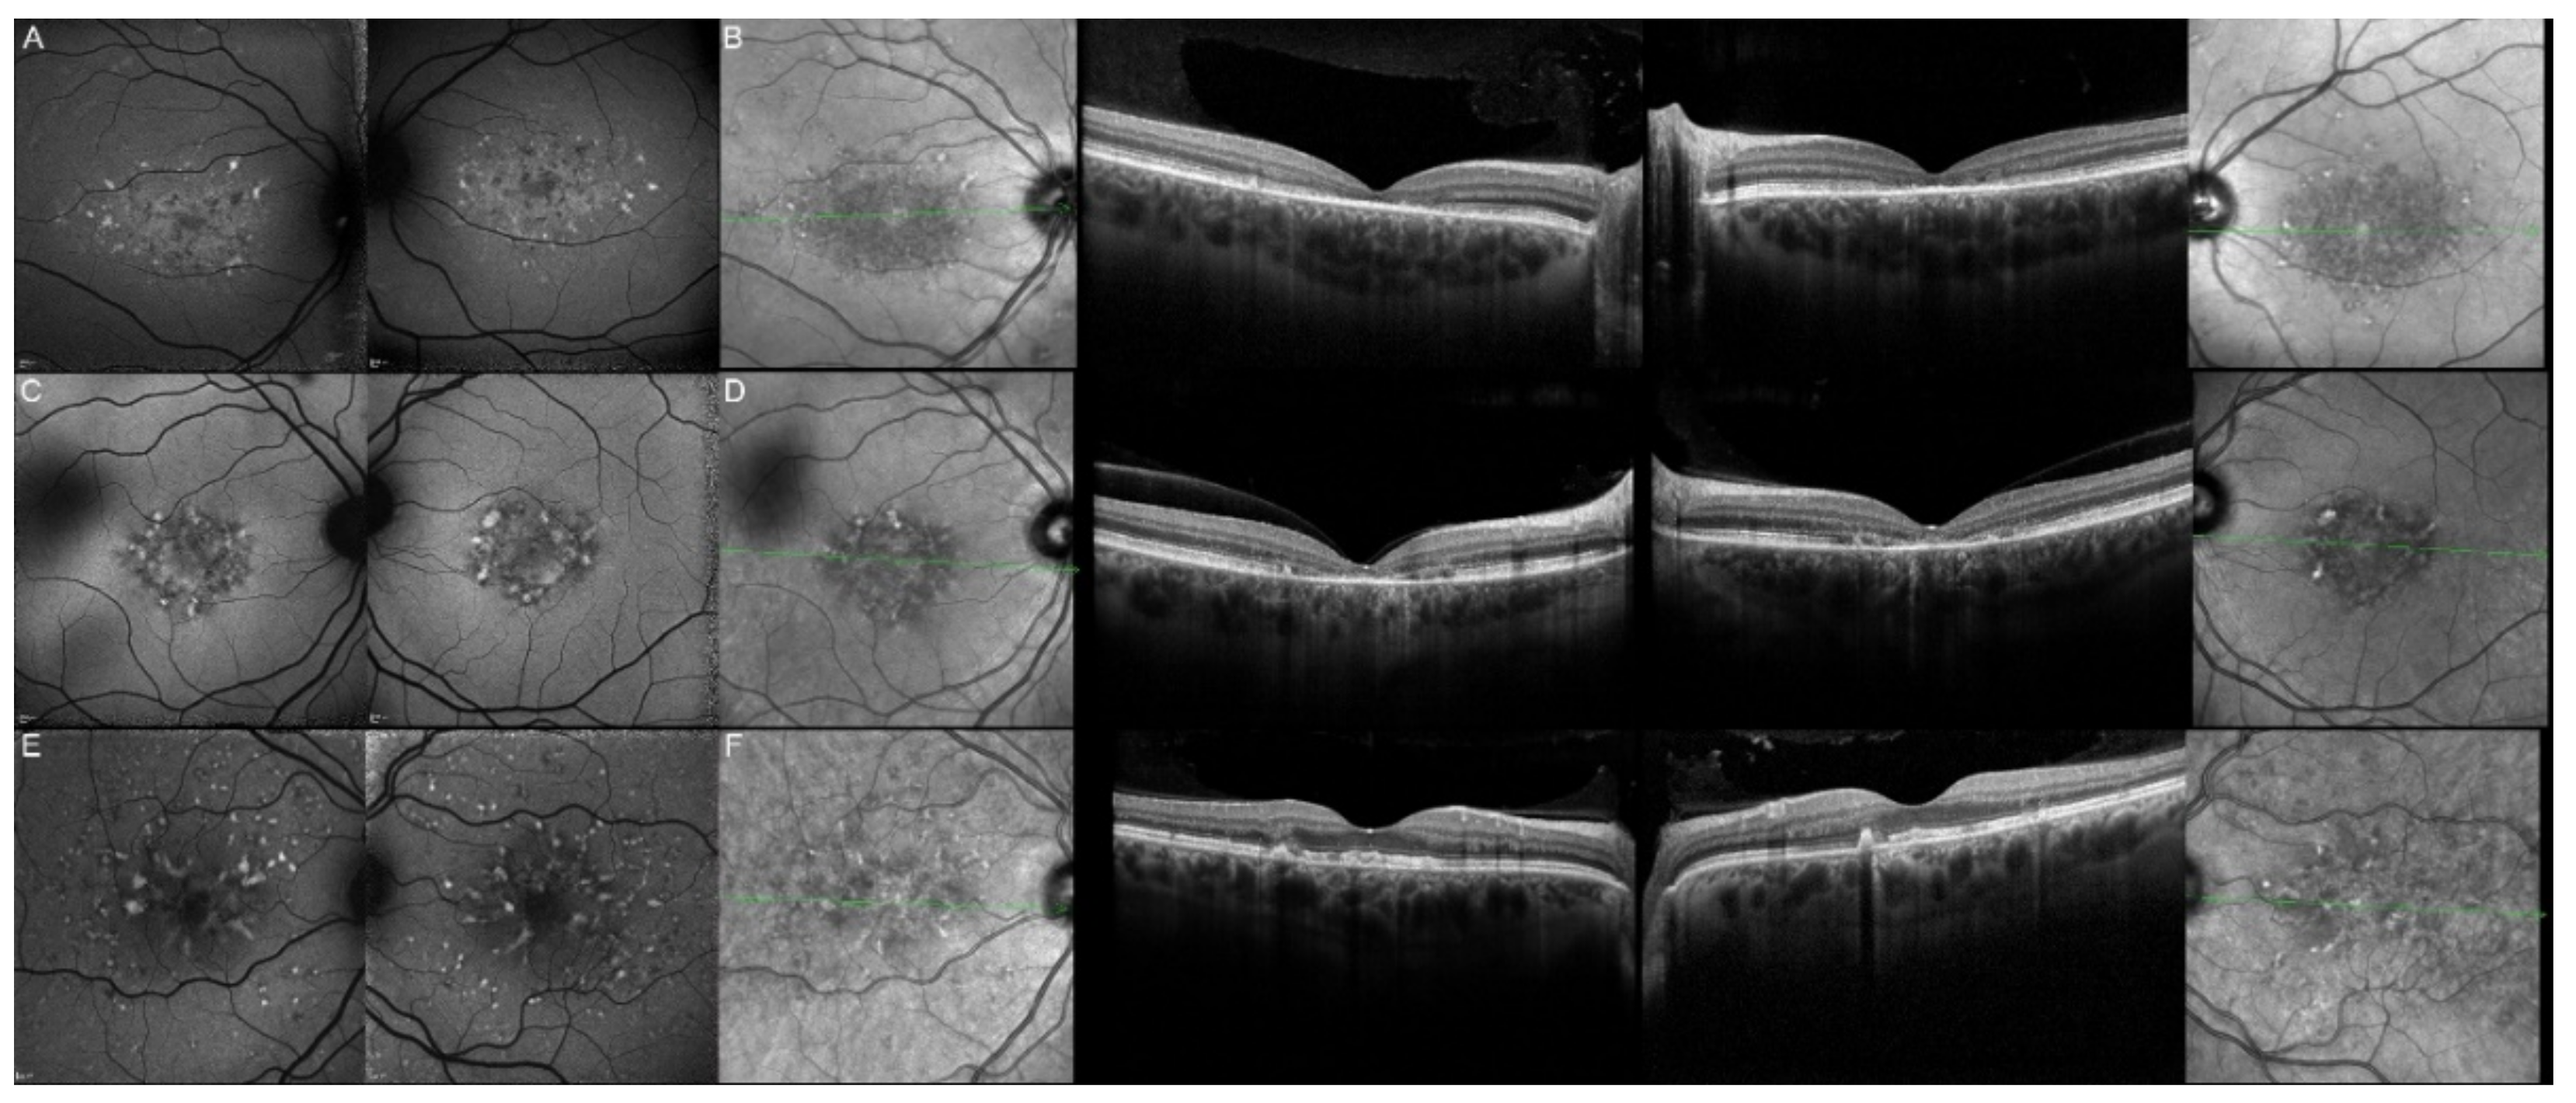

| 17, II.1 | PRPH2 | 51 | F | Butterfly pattern of HPAF and HOAF flecks; paramacular to mid-peripheral HPAF flecks | Irregular EZ thickening |

| 18, II.2 | PRPH2 | 69 | M | Subfoveal HOAF (OS); butterfly pattern of HPAF and HOAF flecks; paramacular to mid-peripheral HPAF flecks | Central EZ loss (OS); central ONL atrophy (OS); localised ONL thinning (OD) |

| 19, III.2 | PRPH2 | 39 | F | Central areolar HOAF; disseminated nummular HPAF | Extended retinal atrophy |